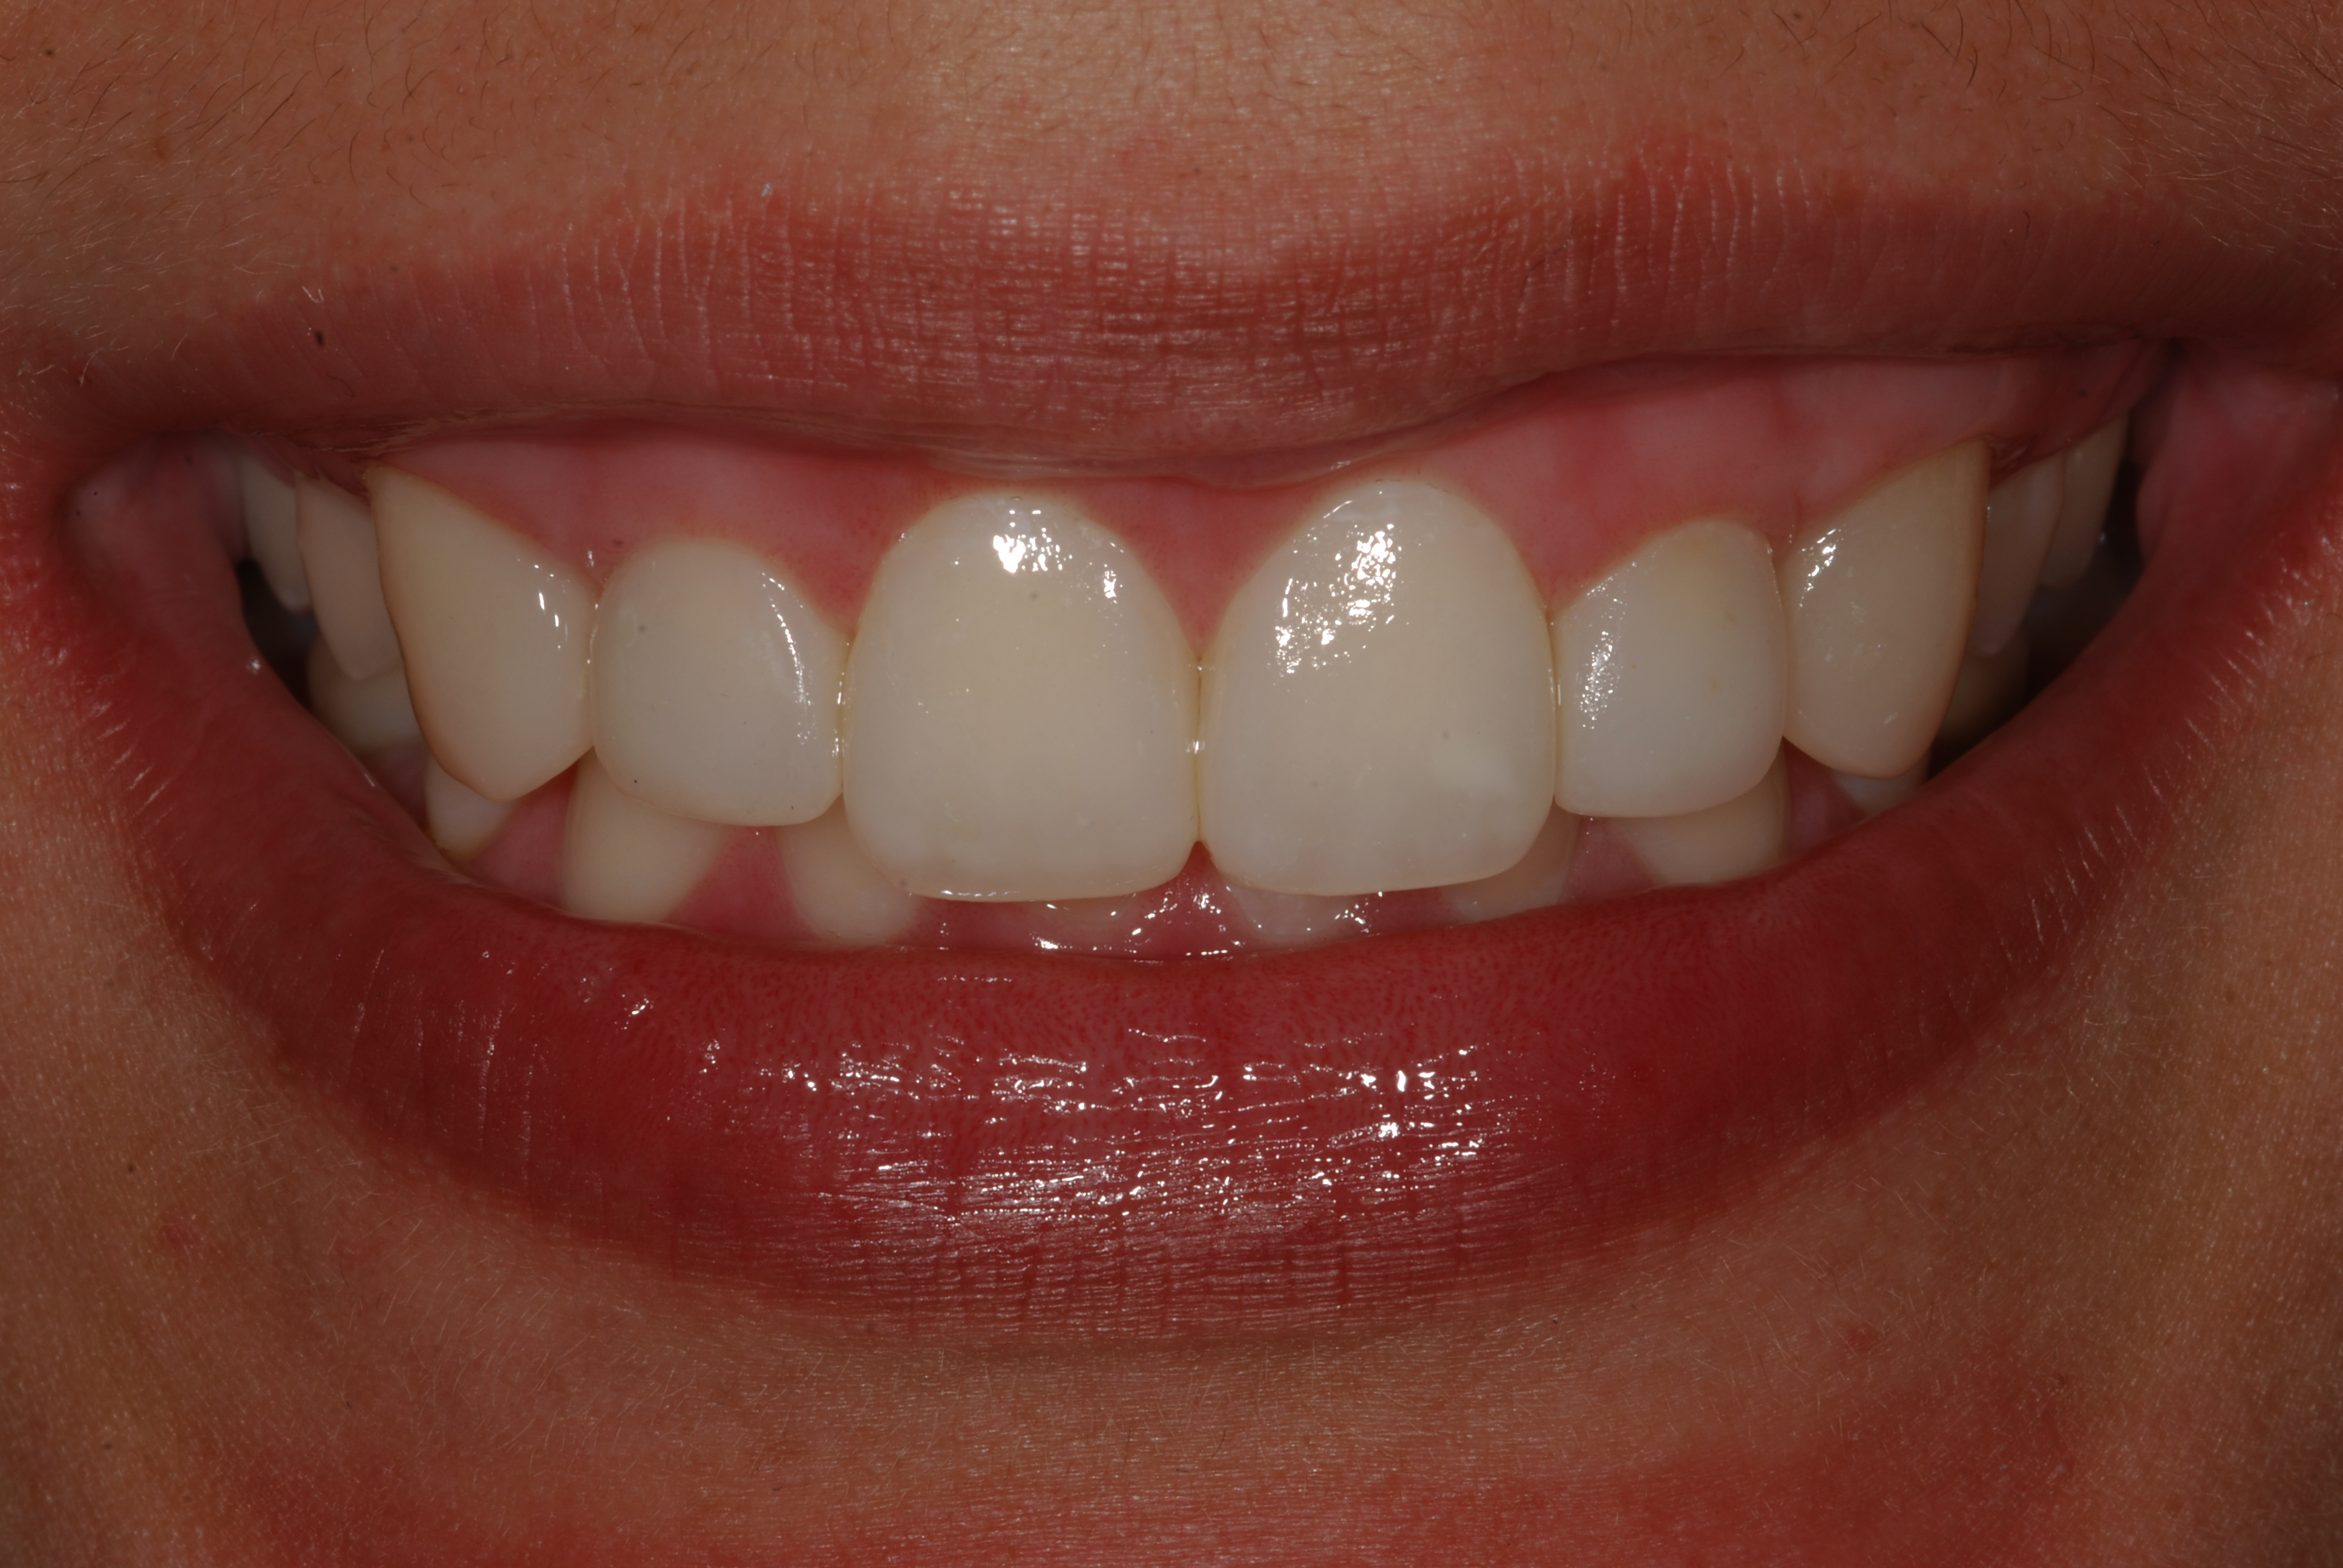

The presence of diastema, between anterior teeth, distorts a pleasing smile by concentrating the observer’s attention on the spaces. The patient’s needs and expectations must be considered in the process of treatment planning to ensure satisfaction with the treatment outcomes. There are many forms of therapy that can be used for diastema closure. A carefully developed diagnosis, which includes a determination of the causal elements and advanced treatment planning, allows the most appropriate treatment to be selected for each case. The aim of this paper is present a multidisciplinary approach as a solution to multiple diastemas in the anterior region using gingival tissue recontouring and direct adhesive restorations, with minimum wear of the dental structure, after the orthodontic intervention discussing the minimal intervention to obtain imperceptive and aesthetic final restoration. Thirty-six months after the treatment was carried out, the final aesthetic was maintained with all dental element details and gingival tissue harmony, without recurrence of periodontal pockets and the preservation of the tooth color and shape.